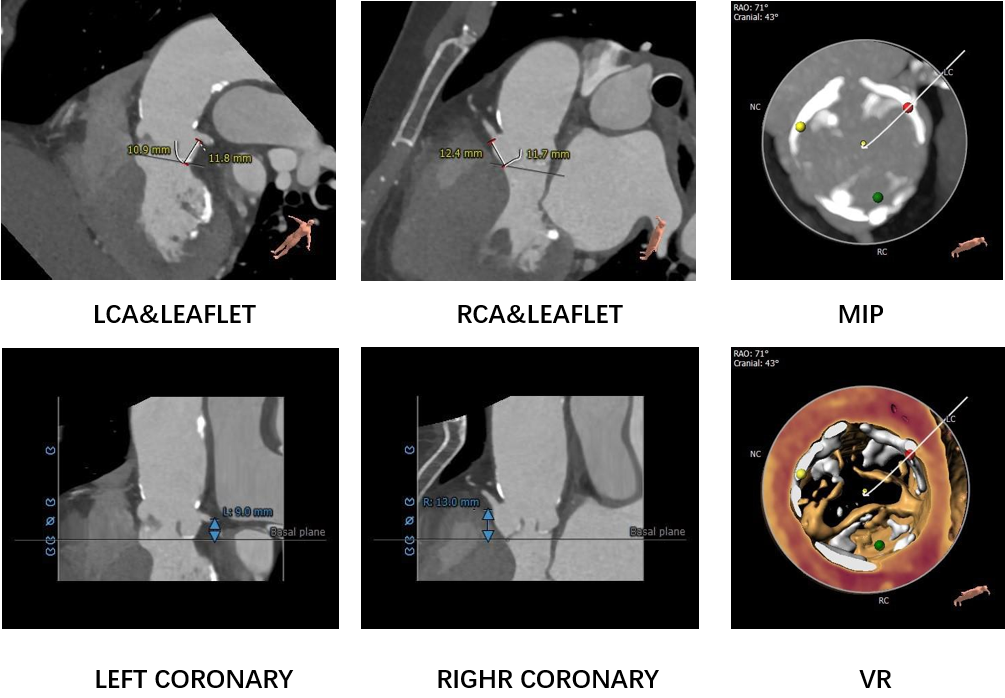

冠脉高度、瓣叶长度及钙化测量

该患者为一个三叶式主动脉瓣,中度钙化,瓣环上2mm-4mm区域钙化较重,提供充足锚定力的同时也可能挤压假体瓣膜造成瓣周漏。左冠高度9.8mm,根据瓣叶长度、瓦氏窦高度、钙化分布预估风险不高,术中关注冠脉血流灌注。

该患者为一个三叶式主动脉瓣,左瓣叶轻中度钙化,瓣叶增厚,预估人工瓣膜向下位移风险较低,瓣周漏风险不高

左冠高度稍偏低,根据瓣叶长度、瓦氏窦宽度、钙化分布预估冠脉阻挡风险不高,术中关注冠脉血流灌注